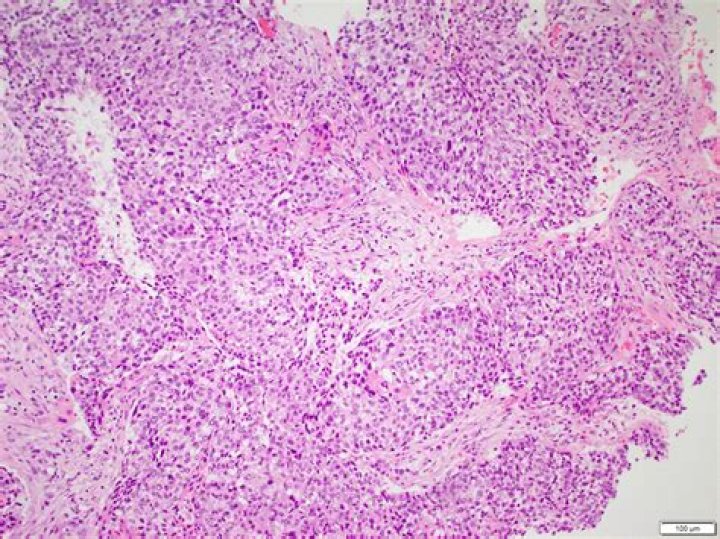

Cutaneous squamous cell carcinoma (SCC) is the second most common skin cancer, most frequently occurring on sun-exposed areas of the body [1]. Bone metastasis from cutaneous SCC is rare.